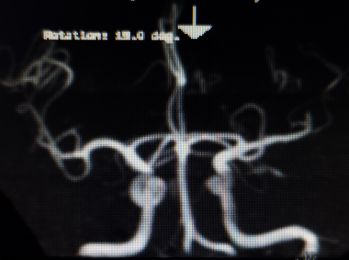

2021年03月01日患者王先生因突发“右侧肢体瘫痪”急诊入院,病情危重,急诊科立即启动脑卒中中心绿色通道,紧急请脑卒中秘书魏华明主治医师会诊,查体结果示:患者处于昏迷状态,完全失语,右侧肢体完全瘫痪,NIHSS评分15分,有急诊取栓的指征,魏大夫立即联系磁共振室完善颅脑血管初步检查,证实了患者为左侧大脑中动脉M2段闭塞所致脑梗死(图一)。家属非常着急,犹豫不定,魏大夫反复向患者家属交代病情,机械取栓越早越好,患者家属最终决心做急诊机械取栓治疗。